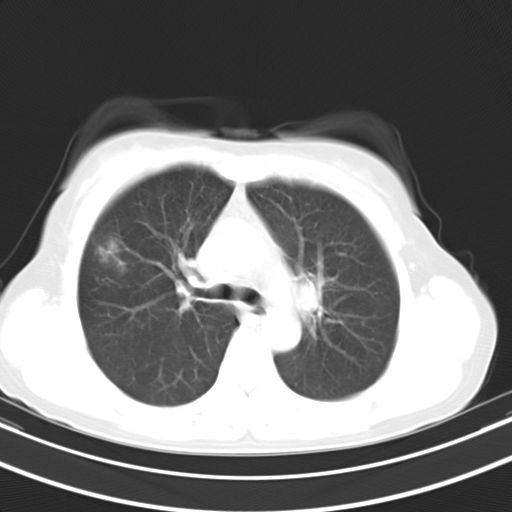

女,47岁,咳嗽胸痛一个星期,我们考虑肺结核,左下肺病灶肿瘤像不像,请高手指点。急。

左上肺舌叶实质性病变,形态呈楔形,内可见支气管气像,中至重度强化,考虑为炎性改变,建议复查

两肺病变考虑炎症可能性大。(左肺病变呈楔状实变影,有支气管气象,近端纹理影增重)。

考虑右肺上叶前段及左肺舌叶炎症,建议抗炎治疗后复查除外结核。

左肺舌叶病灶呈扇形分布,其内可见支气管影,胸膜面光滑,不支持肿瘤病变。